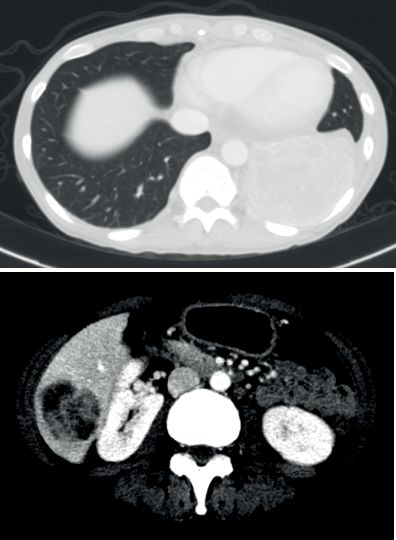

患者4:SQSTM1-NTRK1融合非小细胞肺癌的持久反应

45岁女性被诊断患有IV期NSCLC腺癌,肝脏和纵隔转移以及肥厚性骨关节病(HOA)症状,她曾接受过以前的铂类和培美曲塞治疗。

基因检测发现,NTRK融合基因,接受larotrectinib100 mg每日两次,出现快速反应,表现为第1周期(研究第8天)HOA症状,咳嗽和疲劳的改善以及第3周期完全没有咳嗽。第54天出现部分反应。反应持续时间> 12.88个月。